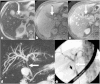

Malignancies of the biliary tract include cholangiocarcinoma, gallbladder cancers and carcinoma of the ampulla of Vater. Biliary tract adenocarcinomas are the second most common primary hepatobiliary cancer. Due to their slow growing nature, non-specific and late symptomatology, these malignancies are often diagnosed in advanced stages with poor prognosis. Apart from incidental discovery of gall bladder carcinoma upon cholecystectomy, early stage biliary tract cancers are now detected with computed tomography (CT) and magnetic resonance imaging (MRI) with magnetic resonance cholangiopancreatography (MRCP). Accurate characterization and staging of these indolent cancers will determine outcome as majority of the patients' are inoperable at the time of presentation. Ultrasound is useful for initial evaluation of the biliary tract and gallbladder masses and in determining the next suitable modality for further evaluation. Multimodality imaging plays an integral role in the management of the biliary tract malignancies. The imaging techniques most useful are MRI with MRCP, endoscopic retrograde cholangiopancreatography (ERCP), endoscopic ultrasound (EUS) and positron emission tomography (PET). In this review we will discuss epidemiology and the role of imaging in detection, characterization and management of the biliary tract malignancies under the three broad categories of cholangiocarcinomas (intra- and extrahepatic), gallbladder cancers and ampullary carcinomas.